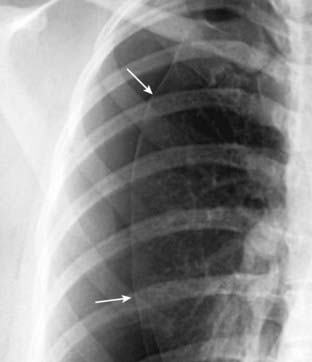

Figure 8-9 Pneumothorax with no shift.

A large left-sided pneumothorax (solid white arrows) demonstrates no shift of the heart or trachea to the right. Subcutaneous emphysema is seen in the region of the left shoulder (solid black arrow). Can you detect why the patient had all of these findings? Yes, that’s a bullet superimposed on the heart (but on CT it was posterior to the heart in the left lower lobe).

Figure 8-10 Large left-sided tension pneumothorax.

Progressive loss of air into the pleural space through a one-way check-valve mechanism may cause a shift of the heart and mediastinal structures away from the side of the pneumothorax and lead to cardiopulmonary compromise by impairing venous return to the heart. In this patient with a spontaneous pneumothorax, the left lung is almost totally collapsed (solid white arrow) and the trachea (solid black arrow) and heart have shifted to the right. The left hemidiaphragm is depressed because of the elevated left intrathoracic pressure (dotted white arrow).